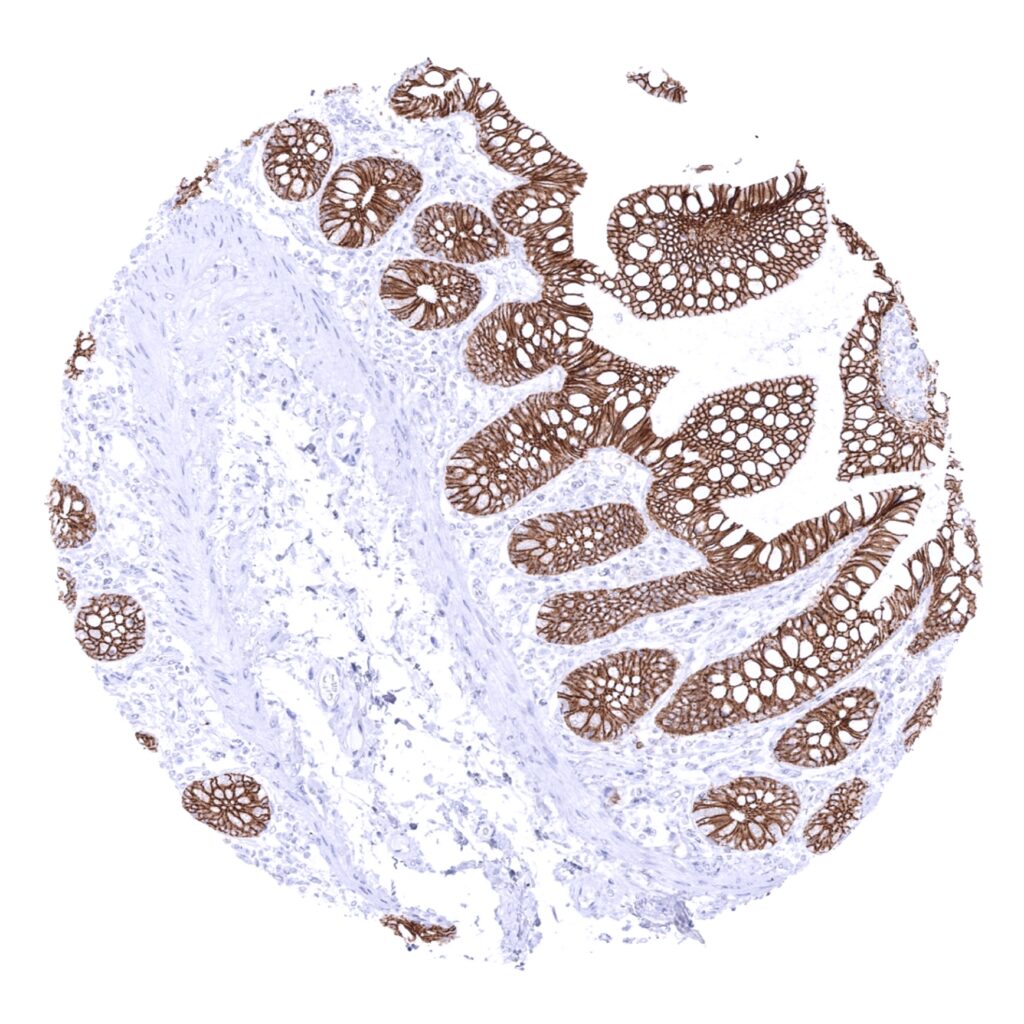

E-Cadherin antibody [MSVA-035R] HistoMAX

Colon descendens, mucosa

Colon descendens, muscular wall